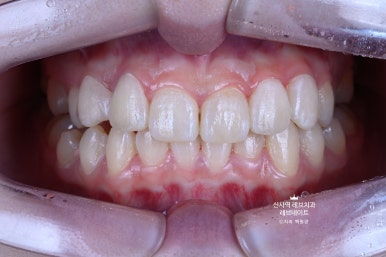

그냥 얼핏 보기엔 뭐.. 치열이 조금 틀어져 있네? 이 정도라고 생각이 드실텐데요

(저 또한 그랬습니다.)

이게 왠걸 ! 고개를 돌려보니 치아가 하나 없는겁니다...

어딨지? 하고 보니,

오른쪽 송곳니가 보다 안쪽에 있는 부정교합이라, 마치 치아하나가 없는 것 처럼 보이는 상태셨어요.

정면만 딱 보면 안보이는 것 같은데, 얘기하거나 웃을 때 엄청 잘 보이는 앞니 사이 공간이 있는거에요..

그리고 잘 보면, 치아들이 조금 뻐드러져 있기도 하고.. 뭔가 돌아가 있기도 하고..

다시 한 번 자세히 보면, 치아 색이 꽤 얼룩덜룩해보이는 것을 아실 수 있을거에요.

위에 있는 사진은 치아를 부드럽게 다듬고 나서 모습입니다.

가운데 앞니 두개가 참 따라하기 어렵게 생겼습니다..

입 안에서 보면 더 자연스럽습니다.

가로로 길어보이는 치아는 이 정도 웃어서는 보이지 않아요. ㅎㅎ

지금 보면 이제 자연스러워 보이는 이 모습이

원래는 이런 부정교합의 모습이었다는 것!

비교해보면 더 확연히 마음에 닿으실 거에요.

뭔가 가지런히 정돈되서, 환자분도 저희들도 만족하고 뿌듯했던 케이스였습니다!